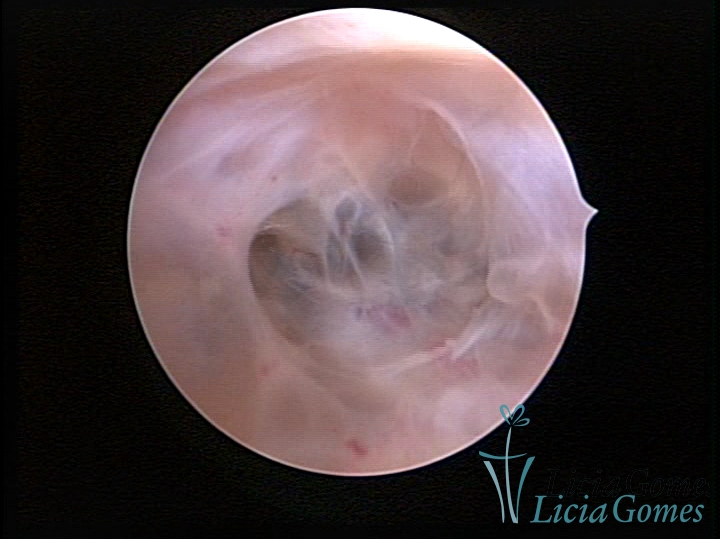

SINÉQUIA TIPO MUCOSA